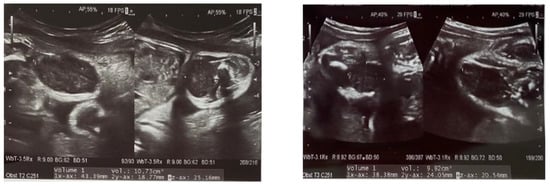

We report the case of a 2 months old female, presented for consultation due to the presence of a lump on her left thigh, with progressive and constant growth after birth. The lesion was first described on the prenatal ultrasound at 30 weeks of gestation as a pre-femoral soft tissue mass of 20/7 mm (Figure 1). The patient was delivered by cesarean section due to fetal distress but was otherwise normal at birth. Development was normal, and there was no relevant family history. On clinical examination, there was a 25/10 mm nodule on the antero-intern side of the left thigh that was firm, mobile and within the deep layers. The overlying skin was normal. There were no other lesions elsewhere on the patient’s body.

Figure 1. Prenatal ultrasound images at 30 weeks of gestation, showing an oval mass, hypoechoic with calcification on the thigh, with no evidence of bone involvement.